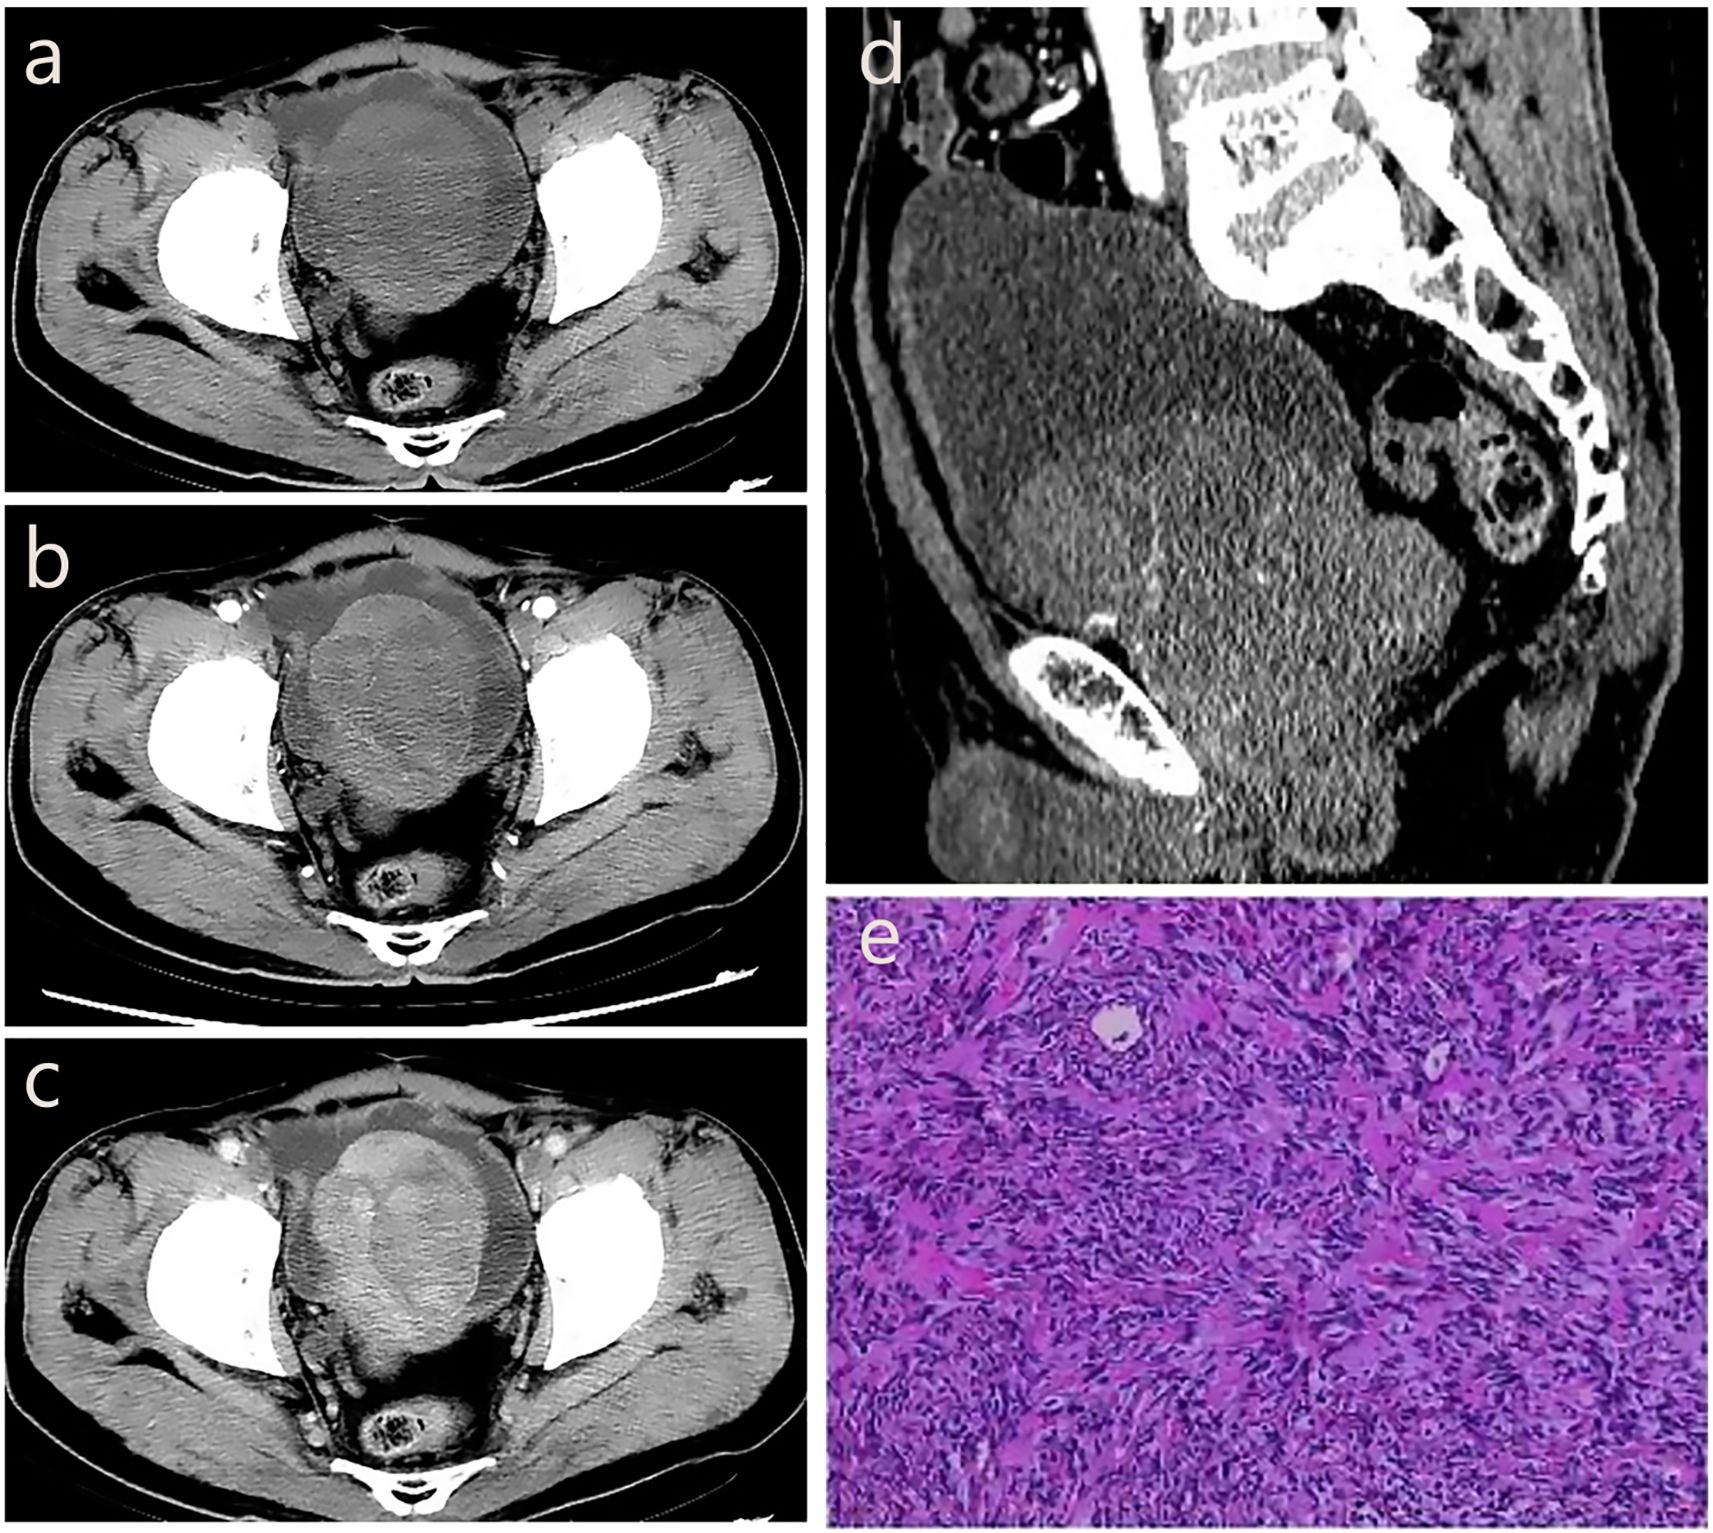

A 71-year-old male patient was admitted to the hospital due to dysuria for more than 3 months and condition worsened for one day. Before admission, the patient had no obvious hematuria, abdominal pain, palpitation, chest tightness and other discomfort. Laboratory tests showed that prostate-specific antigen (PSA=1.99 ng/mL) and free prostate-specific antigen (f-PSA=0.18 ng/mL) were within the normal range. Urine routine tests showed elevated levels of urinary protein (Pro=2g/L), urinary occult blood (BLD=3), and urinary white blood cells (WBC-F=40.6 cells/μL). CT suggested an increase in prostate volume, with a mass of approximately 4.5 cm×5.8 cm protruding into the bladder, with clear boundaries and low density. CT enhanced scan achieved mild enhancement, which is flocculent and uneven. In the venous phase, the tumor indicated continuous and gradual enhancement from the periphery to the center, with visible separation and capsule (Figures 3a–d).

Figure 3. The CT imaging biomarkers and pathological of our pSFT. (a, d) CT shows an increase in prostate volume, with a mass of approximately 4.5cm × 5.8cm protruding into the bladder, with clear boundaries and low density. (b) CT enhanced scan shows mild enhancement in the arterial phase, which is flocculent and uneven. (c) In the venous phase, the tumor shows continuous and gradual enhancement from the periphery to the center, with visible separation and capsule. (e) Pathological examination showed a spindle cell tumor of the prostate, and the tumor cells were spindle-shaped, wavy, storiform or fascicular arrangement, and hemangiopericytoma-like structure could be seen and nuclear division was clear to see, spindle-shaped or oval.

The patient underwent transurethral resection of the prostate (TURP) under spinal anesthesia 6 days after admission. During the operation, the bilateral lobes of the prostate were obviously hyperplasia into the cavity, the posterior lip of the bladder neck was moderately elevated, and a round mass with a size of about 4cm×5cm was seen at about 11 o’clock of the prostate projecting into the urethra. Postoperative pathological examination showed a spindle cell tumor of the prostate, and the tumor cells were spindle-shaped, wavy, storiform or fascicular arrangement, and hemangiopericytoma-like structure could be seen and nuclear division was clear to see, spindle-shaped or oval (Figure 3e). The immunohistochemistry results showed CK (–), P63 (–), P504S (–), S100 (–), CD34 (+), BCL-2 (+), CD99 (+), SMA (–), Desmin (–), 10%-20% Ki-67-positive. The result of pathological diagnosis was pSFT. Notably, the patient was followed up in the outpatient department for 3 years after surgery, and there were no signs of recurrence.